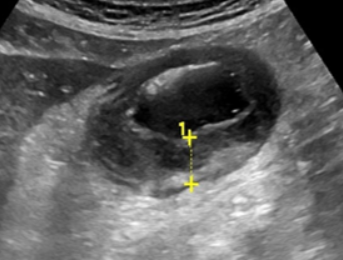

Duplication cyst